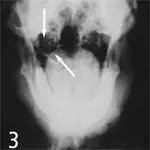

Lateral Oblique Views

1. Normal Canine Tympanic Bulla: Normal tympanic bulla in a dog appears as a thin-walled, crisply outlined structure with a smooth external border (arrow).